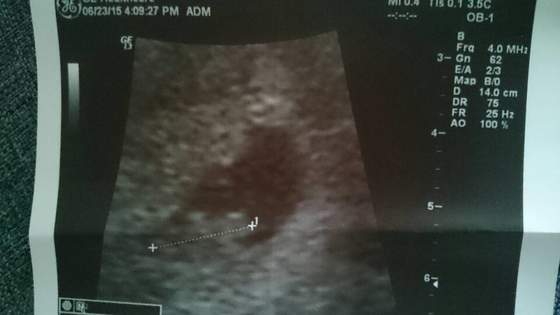

w środę zaraz po powrocie z urlopu zrobiłam test ( no dobra - 3 testy

) i na każdym dwie krechy

w piątek gin potwierdził ciążę

znowu udało nam się w pierwszym cyklu, więc jestem szczęśliwa :-)